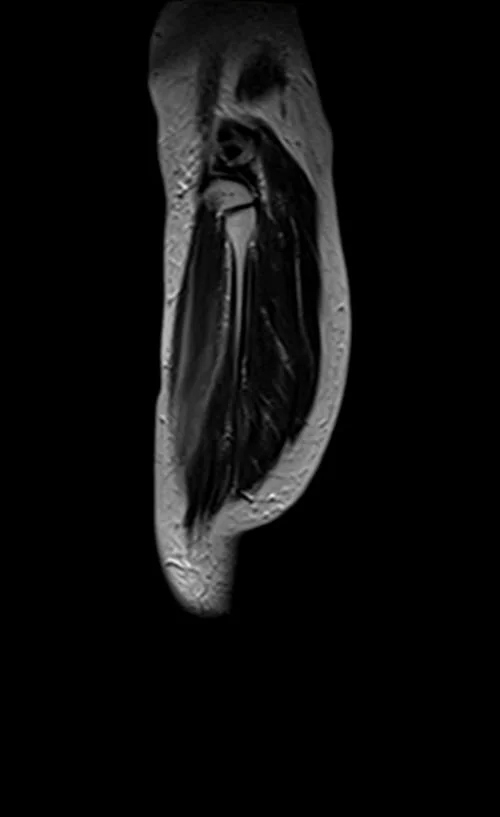

mri lower legs (calves) t2 sagittal image 2 - MRI